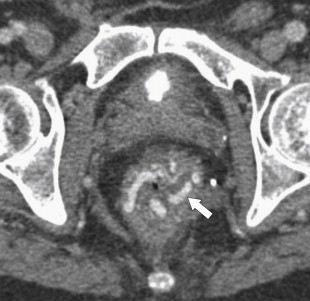

The imaging findings may lag behind the clinical features, and patients may have pronounced clinical disease without obvious imaging findings. When observed, the imaging features are similar to most other colitides. Plain radiography often demonstrates ileus and, as the disease progresses, nodular haustral thickening, often over a long segment because the disease usually presents as a pancolitis. There may be polypoid mucosal thickening representing the pseudomembranes, but this is not often observed ( Fig. 5-45 ). The disease can progress readily to frank toxic megacolon. However, it is optimally evaluated by CT, which demonstrates bowel wall thickening, mucosal enhancement, often with a mural stratification (or target sign representing unenhanced thickened submucosa surrounded by enhancing mucosa and muscularis propria), pericolonic edema, and mild ascites. The bowel wall thickening is often pronounced, more so than in other colitides, with the thickened haustra giving the appearance of an accordion pattern (also found with CMV colitis) over a relatively long segment of bowel ( Fig. 5-52 ), representing oral contrast material trapped between the bulbous-thickened haustra.

Figure 5-52, Axial contrast-enhanced CT in a 46-year-old woman with pancolitic mucosal thickening ( arrow ) due to Clostridium difficile colitis. The haustral thickening in the right colon conforms to the “accordion pattern.”